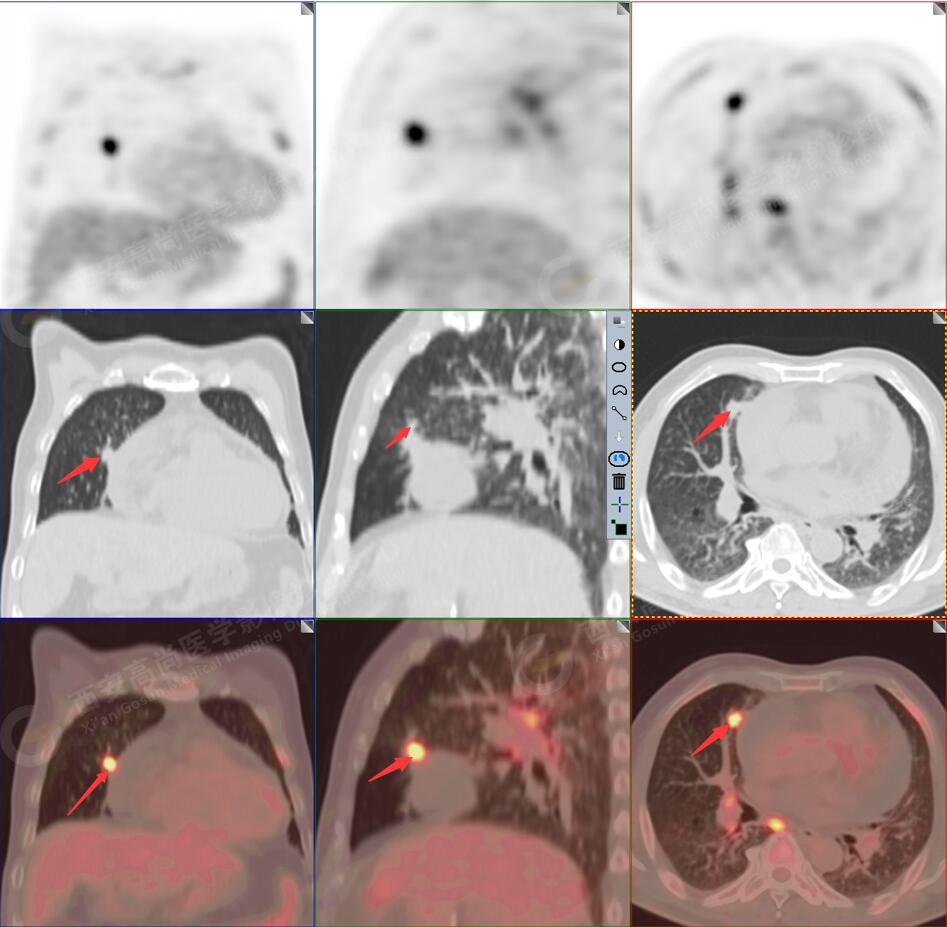

2.以下為全身多發(fā)轉移灶

2.雙肺內(nèi)彌漫性分布大小不等實性小結節(jié)灶及粟粒狀高密度影,均未見FDG代謝明顯異常增高,均多考慮為癌性淋巴結炎及轉移性病變。

3.右側頸部(Ⅱ-Ⅴ區(qū))、右側腋窩區(qū)、右側肺門及縱隔(1R、1L、2、4、6、7組)、肝門區(qū)多發(fā)腫大淋巴結,呈不同程度異常增高,均考慮為淋巴結轉移。